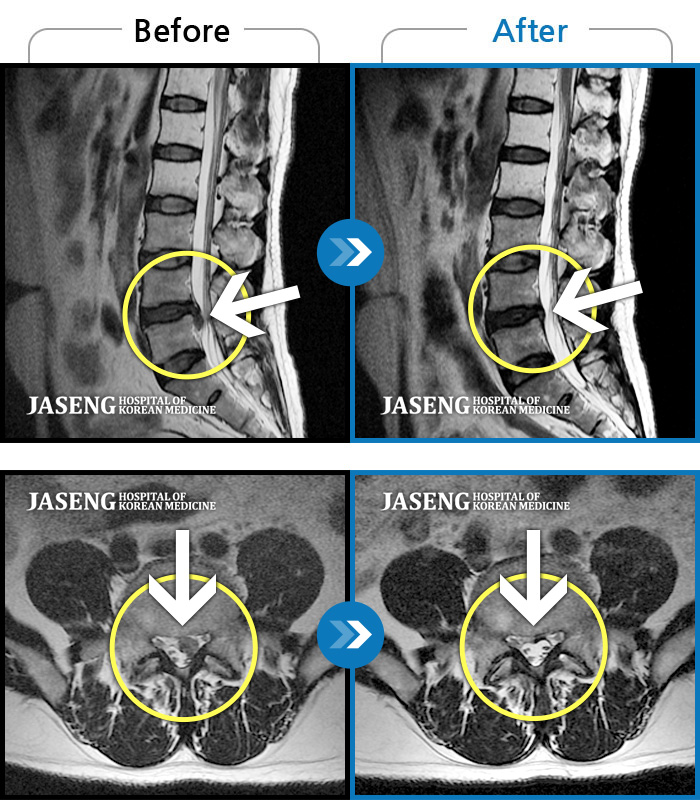

허리디스크

보라매 · 빈상은 원장

좌측 허리부터 고관절 통증이 심하고 다리까지 저려서 허리를 똑바로 펴기 힘들어요.

촬영시기

2020.07.27 ~ 2023.01.20

2023.11.24

조회수 468